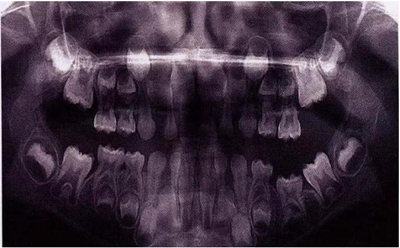

圖8展示了一張5歲孩子右下第二乳磨牙嚴(yán)重下沉的口內(nèi)像。臨床檢查可見右下第一乳磨牙遠(yuǎn)中傾斜,朝向下沉乳牙。X線片檢查顯示所有恒牙胚都存在(圖9)。無論是臨床還是影像學(xué),都可檢查到有齲齒的存在。鑒于這顆下沉乳牙在年齡較小時(shí)就已經(jīng)非常嚴(yán)重,同時(shí)還患有齲病,因此決定予以拔除。后期在放置間隙保持器的同時(shí)還應(yīng)持續(xù)觀察監(jiān)測(cè)右下第一恒磨牙和第二前磨牙的萌出情況。

文獻(xiàn)直達(dá)|乳磨牙下沉的臨床管理

圖8:一名五歲患兒右側(cè)下頜第二乳磨牙嚴(yán)重下沉臨床像

圖9:一名五歲患兒右側(cè)下頜第二乳磨牙嚴(yán)重下沉的曲面體層片